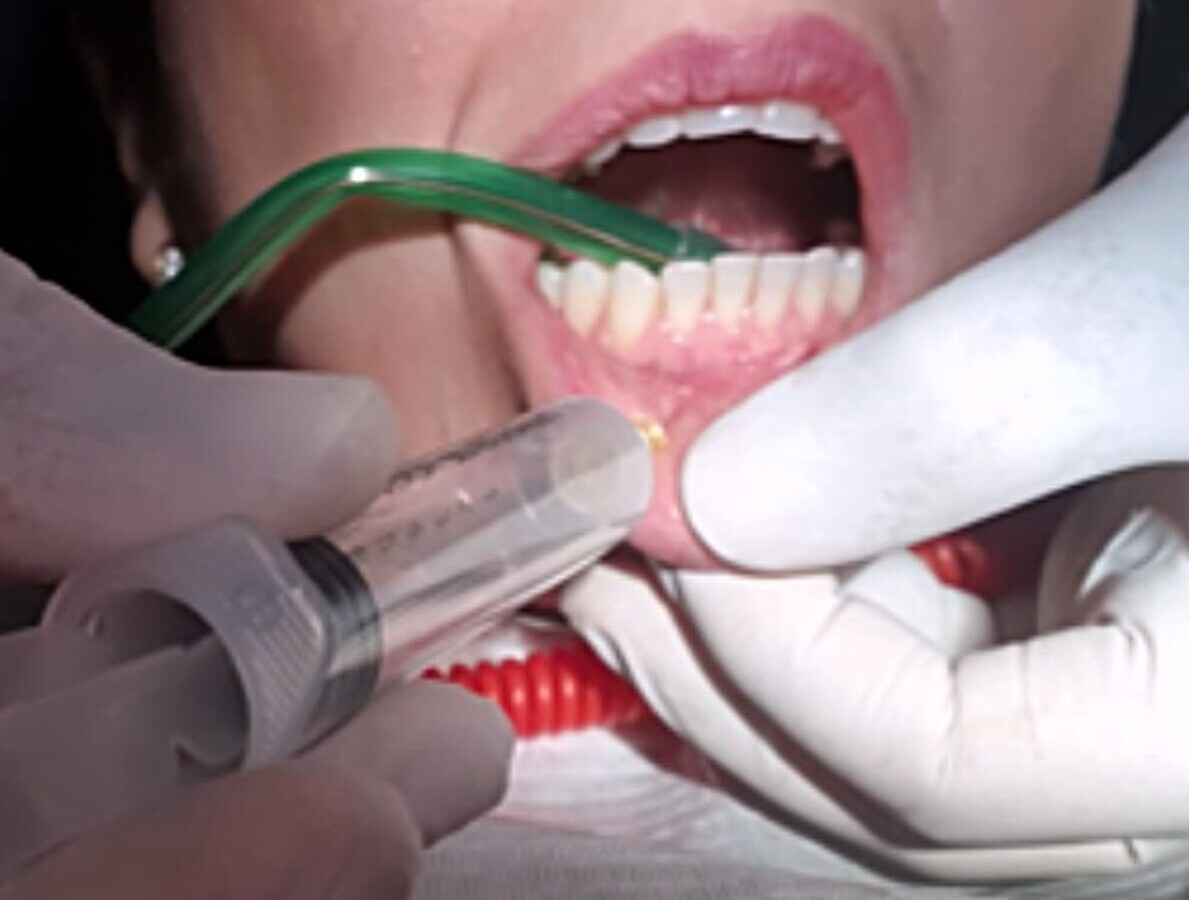

2. Aplicación anestésica infiltrativa en fondo de surco, a la altura de la lesión existente con medio tubo de lidocaína al 0,2% con epinefrina, previa anestesia tópica local (Figura 2).

Figura 2. Aplicación anestésica infiltrativa a la altura de la lesión con lidocaína al 0,2% con epinefrina, previa anestesia tópica local.